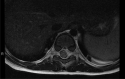

Case description: We report a case of spontaneous pediatric SEA in a 22-month old female without obvious neurologic deficit, who underwent a T10-11 decompressive laminotomy and evacuation of abscess and subsequent 3-week course of intravenous ceftriaxone for culture positive S. pyogenes.